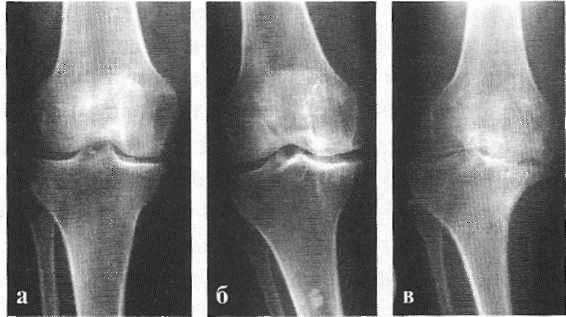

В травматологии и ортопедии диагноз кисты менисков выставляется на основании клинической картины, результатов УЗИ коленного сустава, артроскопии или МРТ коленного сустава. При развитии деформирующего артроза мыщелка большеберцовой кости выявляются характерные изменения на рентгенограммах (симптом Раубера-Ткаченко).

По данным исследователей, у 76% пожилых людей, предъявляющих жалобы на боль в коленях, на рентгенограммах обнаруживается гонартроз. [2] [7] [17] По статистике, чаще заболеванием страдают женщины, что связано с гормональной перестройкой после 45 лет. [12] [19]

В подавляющем большинстве случаев достаточно осмотра и рентгенограммы коленного сустава в двух проекциях (прямой и боковой). [2] [19] Клинические данные и снимки позволяют определить стадию заболевания.

На ранних стадиях заболевания, при незначительных изменениях в костной ткани, рентгенологическое обследование не настолько ценно. [5] [8] На этом этапе гонартроз возможно диагностировать благодаря артроскопии. [5] [8] Точность метода очень высока, останавливать может только его инвазивный характер и цена.